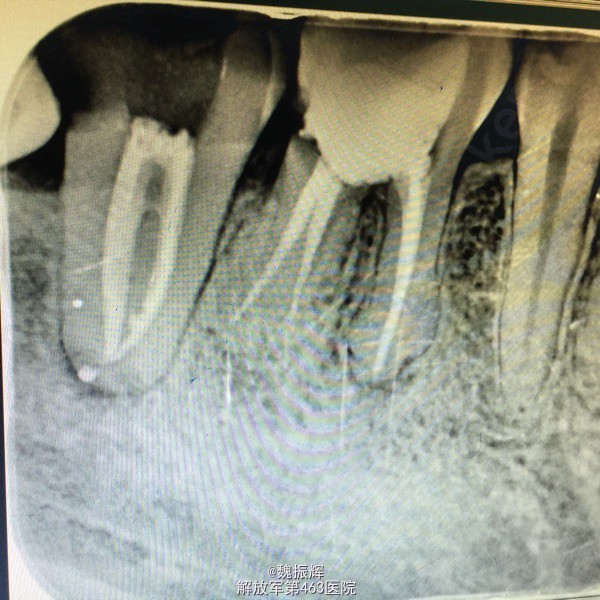

查体:47远中邻面龋坏,探(+),冷(+),叩(-),X线示远中龋坏近髓,48近中阻生,47,48之间食物嵌塞。

诊断:牙髓炎 处理:局麻下,47降牙合,去腐,开髓,揭髓顶冲洗,拔髓,根管疏通测量及机用镍钛器械进行根管预备,次氯酸钠进行根管冲洗,大椎度牙胶尖试尖,进行根管充填。Zoe暂封,观察嵌体修复。择期拔除48。